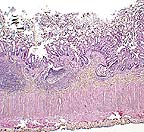

Case III -96-36 (AFIP 2548683)

Signalment: Common marmoset.

Several adult spirurid nematodes within pancreatic ducts in a marmoset infected with Trichospirura leptostoma. *HE, 40X, 120K)

History: Several similarly housed marmosets presented clinically with a syndrome similar to "marmoset wasting syndrome" (weight loss and failure to thrive).

Gross Pathology: In affected animals, gross pancreatic lesions were minimal and indicative of chronic pancreatitis.

Contributor's Diagnosis and Comments: Pancreas: Pancreatitis, lymphocytic, eosinophilic, chronic, multifocal, mild to moderate with intraductal nematodes (Trichospirura leptostoma).

Marked variation is present in the severity of lesions between affected animals. Lesions consist of the following: Multifocally, pancreatic ducts are greatly dilated and contain numerous parasites. The parasites are round, approximately 125 to 150 in diameter, have a ridged cuticle, a pseudocoelom and contain tubular organs (nematode). Numerous embryonated ova are present in the uterus of female parasites. Ductular epithelium is multifocally attenuated and periductal tissue is fibrotic and hypercellular. The cellular infiltrate is composed primarily of lymphocytes with fewer eosinophils. The cellular fibrous tissue extends into exocrine tissue where there is loss of acinar tissue. The morphology and intraductal location of the nematodes are most suggestive Trichospirura leptostoma infection.

Marmoset wasting syndrome is a loosely described disease entity that appears to be multifactorial. In this group of animals, failure to thrive was correlated with the presence of a verminous pancreatitis. Differential diagnosis included nematode larval migration (ex: Strongyloides sp), Angiostrongylus sp. infection and pancreatic trematodiasis.

AFIP Diagnosis: 1. Pancreas: Pancreatitis, chronic-active, multifocal, moderate, with intraductal adult and larval spirurid nematodes, common marmoset, primate. 2. Urinary bladder: Cystitis, transmural, acute, multifocal, moderate.

Conference Note: The spirurid nematode Trichospirura leptostoma has been found within the pancreatic ducts of several species of wild South American nonhuman primates. Infections of captive primates have been reported occasionally. These animals become infected when they ingest an arthropod intermediate host (most likely cockroaches) containing the encysted infective larval stage (L3). The L3 migrate to the pancreatic ducts where they mature into adults. Embryonated eggs travel down the pancreatic duct into the intestine and are passed in the feces. The prepatent period is approximately 7 to 9 weeks. The presence of the adults within the pancreatic ducts may cause compression atrophy of the lining epithelium, pancreatitis, and acinar atrophy.

Characteristic features of spirurid nematodes include coelomyarian, polymyarian musculature, esophagus with anterior muscular and posterior glandular portions, intestine lined by uninucleate cells with a long or medium length microvillar border, prominent lateral chords and thick-shelled embryonated eggs. Excretory canals are present in the lateral chords of this spirurid.